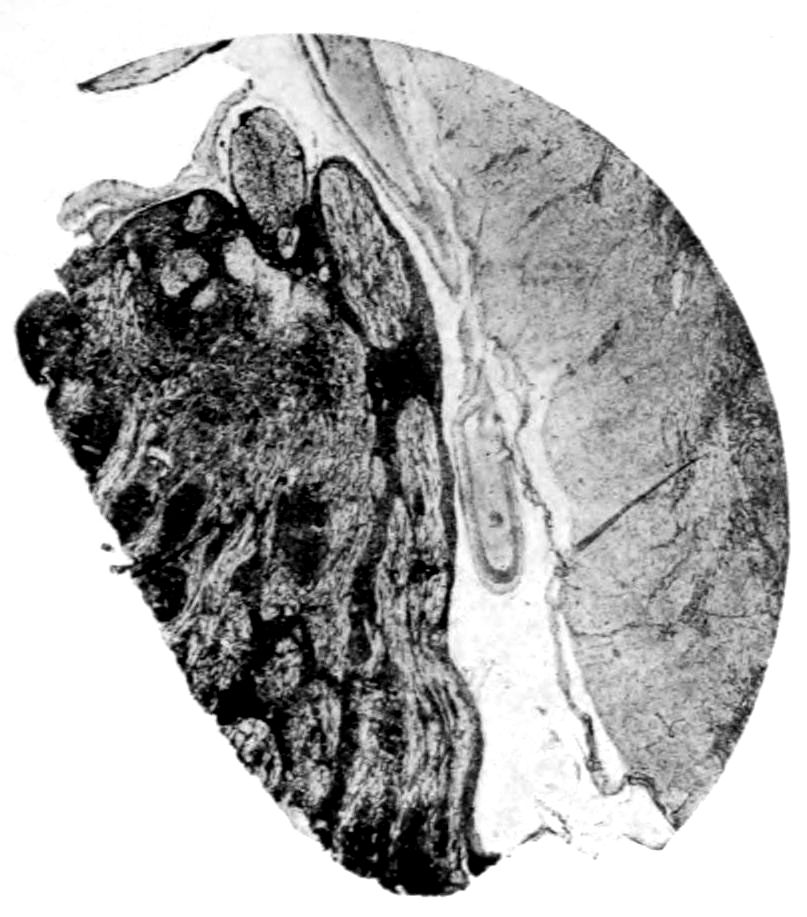

Vascular neurosyphilis—effects of syphilitic thrombosis of Sylvian artery 10 years before death. (Case 4.)

Case 4. (See previous figure for brain lesion.) Three levels of the spinal cord showing unilateral pyramidal tract sclerosis, 10 years after cerebral thrombosis.